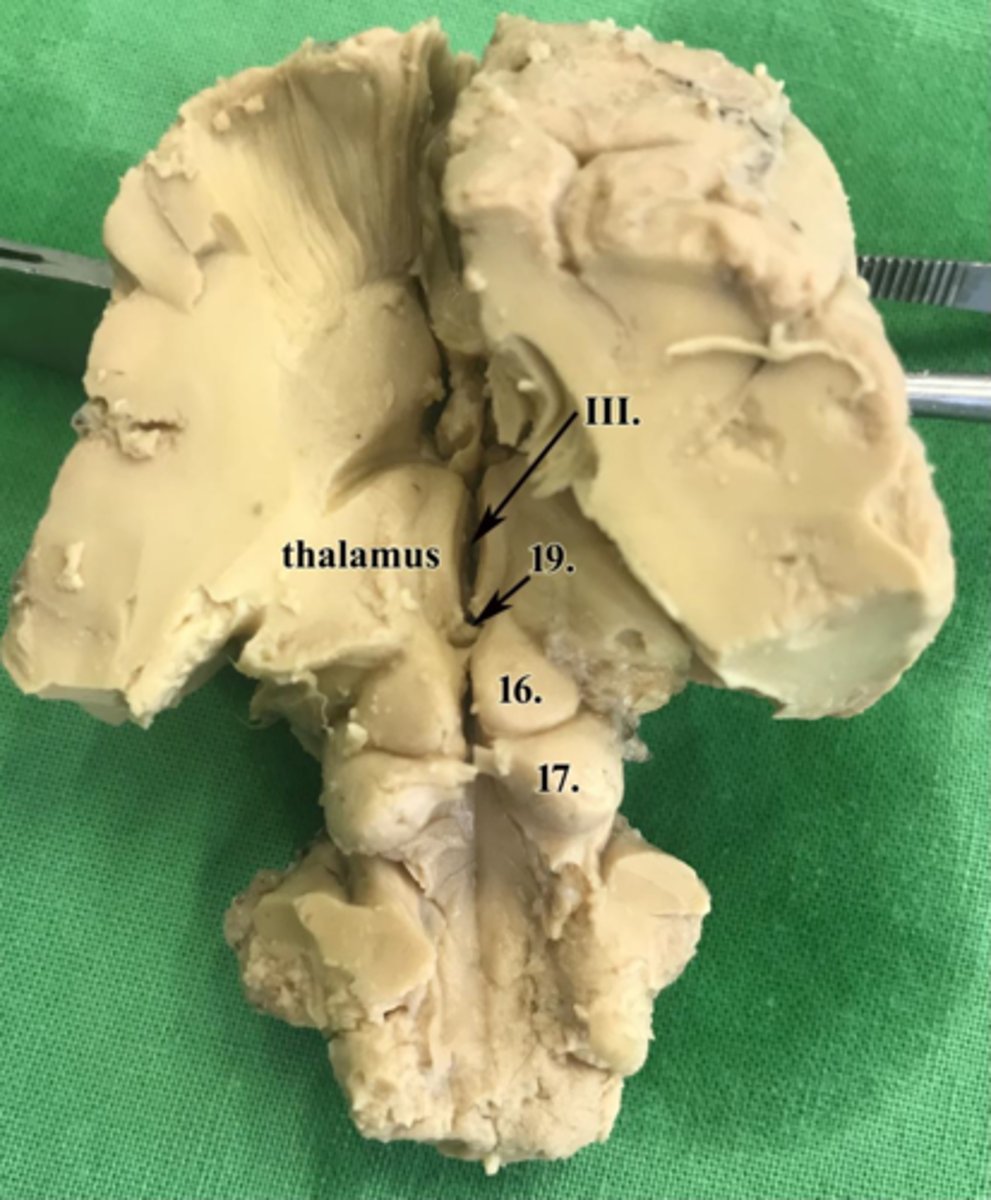

ventriculus tertius

III

adhesio interthalamica

18

colliculi rostrales

16

colliculi caudales

17

glandula pinealis

19